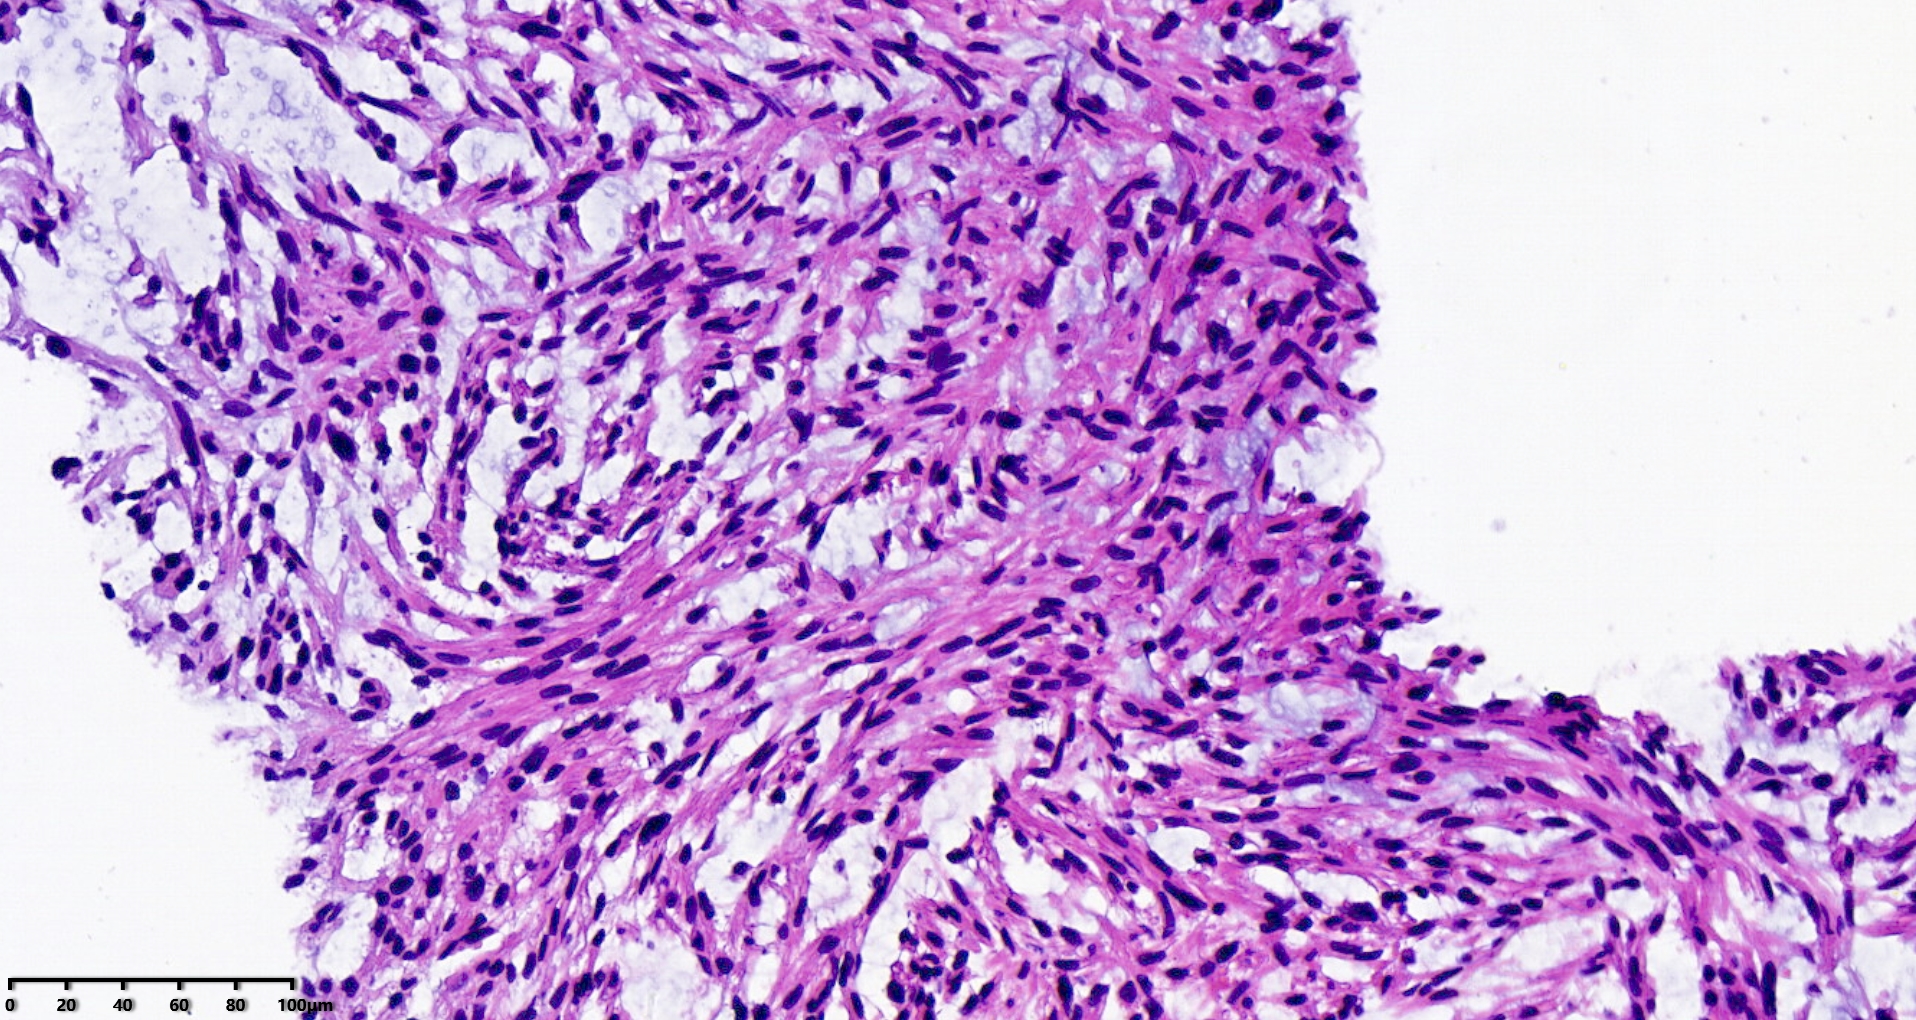

腹盆腔穿刺

腹盆腔肿物10.5×21.5cm大小

穿刺组织1.0×1.0cm

S100、CD34、MDM2、STAT6、CD117、CK均阴性

图1

SMA和Desmin阳了,可以考虑加一下H-cald,ALK,pP6,P53。

考虑:深部软组织平滑肌肉瘤